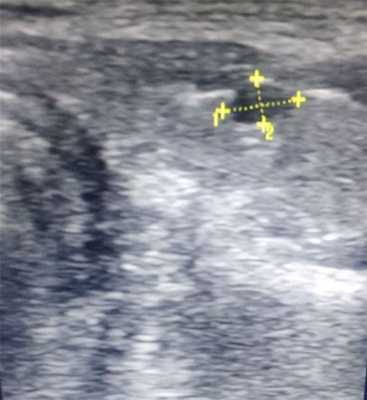

Солидные узлы на УЗИ

Узлы в щитовидной железе обнаруживаются у 50% лиц без симптомов. Злокачественные опухоли щитовидной железы встречаются редко. Тем не менее, дифференциация доброкачественных и злокачественных узелков является проблемой в ультразвуковой диагностике щитовидной железы.

В зависимости от структуры фолликула, аденомы в основном гипоэхогенные (микрофолликулярные) или более эхогенные и довольно однородные. Их контур ровный. Низкая эхогенность при серошкальном сканировании с сосудами вокруг узла характерно для доброкачественной аденомы и поэтому лучше всего демонстрируется с помощью цветного допплера. Горячие аденомы часто проявляют гиперваскулярность.

Злокачественные опухоли высокоэхогенны и слегка неоднородны, хотя неоднородный характер трудно распознать при меньших поражениях. Чрезвычайно низка эхогенность обнаруживается при злокачественных лимфомах и анапластических раках. Отсутствие ореола типично. Контур нерегулярный и может показать псевдокапсулу. Разрыв капсулы щитовидной железы и инфильтрация окружающей ткани также могут быть визуализированы. Когда сагиттальный диаметр больше поперечного диаметра, результаты обычно подозрительны.